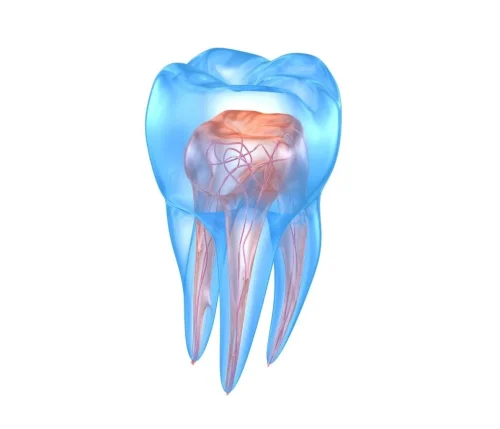

Trattamenti di endodonzia

Baldan Dr. Arianna Medico Odontoiatra esegue anche trattamenti di endodonzia: presso lo studio con sede a Mirano, in provincia di Venezia, abbiamo tutte le conoscenze e gli strumenti per salvare il dente in caso la carie degeneri fino ad attaccare la polpa dentaria.